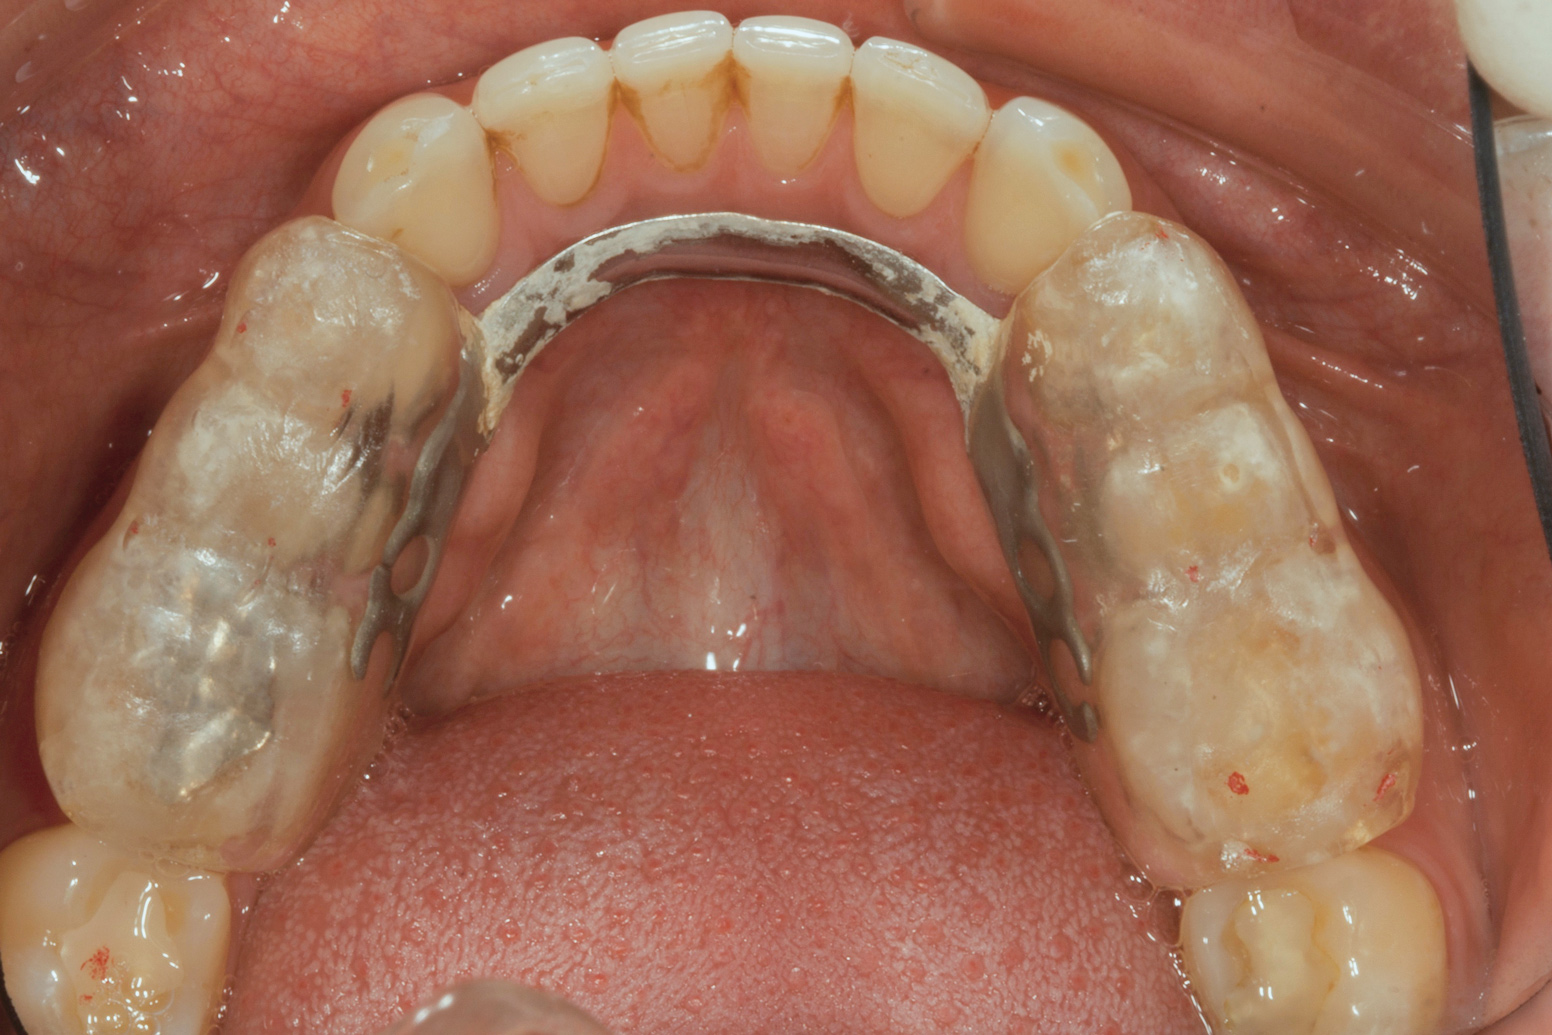

(3.) Preoperative occlusal view of lower arch with orthotic in place.

Figure 3

Ultimately, the patient developed joint and muscle symptoms due to his lack of posterior support and sought the help of a specialist. His bite was analyzed, and he was fitted with a dental orthotic that allowed his teeth to touch in centric relation (Figure 3). This was intended to be a temporary measure to stabilize the patient's bite and make him comfortable, but before any permanent treatment could be carried out, he moved abroad and had been living with the device for more than four years before the time of the consultation. He stated that his bite was now very stable with the orthotic, but he was looking for a more permanent solution and also wanted to improve the overall appearance of his smile.

The patient's removable dental orthotic covered the lower bicuspids and first molars. With the orthotic in place, there was shim stock contact on all posterior teeth and on the second molars that were not covered by the appliance. However, there was no incisal overlap and a lack of anterior guidance.11 When the orthotic was removed, solid shim stock contacts were present on the second molars and the right lateral incisor. These contacts were reproduced every time the appliance was removed. The same contacts were found on the patient's mounted models, which confirmed that the joints were in centric relation. Whether the lower second molars had overerupted as a result of wearing the appliance or had already been in this position before the orthotic was fitted could not be established. Apart from these three contacts, no other teeth touched, and there was a 2-mm space between the posterior teeth, making mastication difficult. Interestingly, wear facets were present on the palatal surfaces of the upper central and lateral incisors, indicating that at some point in time, there had been significant overlap of the anterior teeth and a possible constriction of the chewing envelope. Analysis of a cephalometric radiograph showed a class II growth tendency with a reduced mandibular plane angle, which supported the theory that the patient had at one time possessed a class II occlusion.